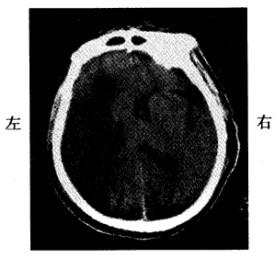

问题 男,60岁。晨睡醒后左侧肢体无力,刷牙时无法拿杯。有糖尿病和高血压史无心脏病史。半天后急诊。查体:左侧肢体肌力3级,腱反射高于右侧,左侧Babin-ski征阳性。左侧肢体痛温觉减退。脑CT见图示:

可能的诊断为

选项 A:脑转移癌 B:脑栓塞 C:短暂性脑缺血发作 D:脑血栓形成 E:高血压性脑出血

答案 D

解析 本题考查目的是综合临床资料和CT图像作出脑血管病的诊断。从上题的脑缺血性卒中与出血性卒中的鉴别要点表中很容易得出答案D脑血栓形成。短暂性脑缺血发作的体征一般1~2小时恢复,而且以单肢瘫等局限体征为多见。CT上一般没有梗死灶。脑栓塞一般在活动状态下,数秒钟即出现明显脑症状,大多数患者有房颤等栓塞灶的来源。这些均与本例不符合,故缺血后卒中以脑血栓形成为正确答案。